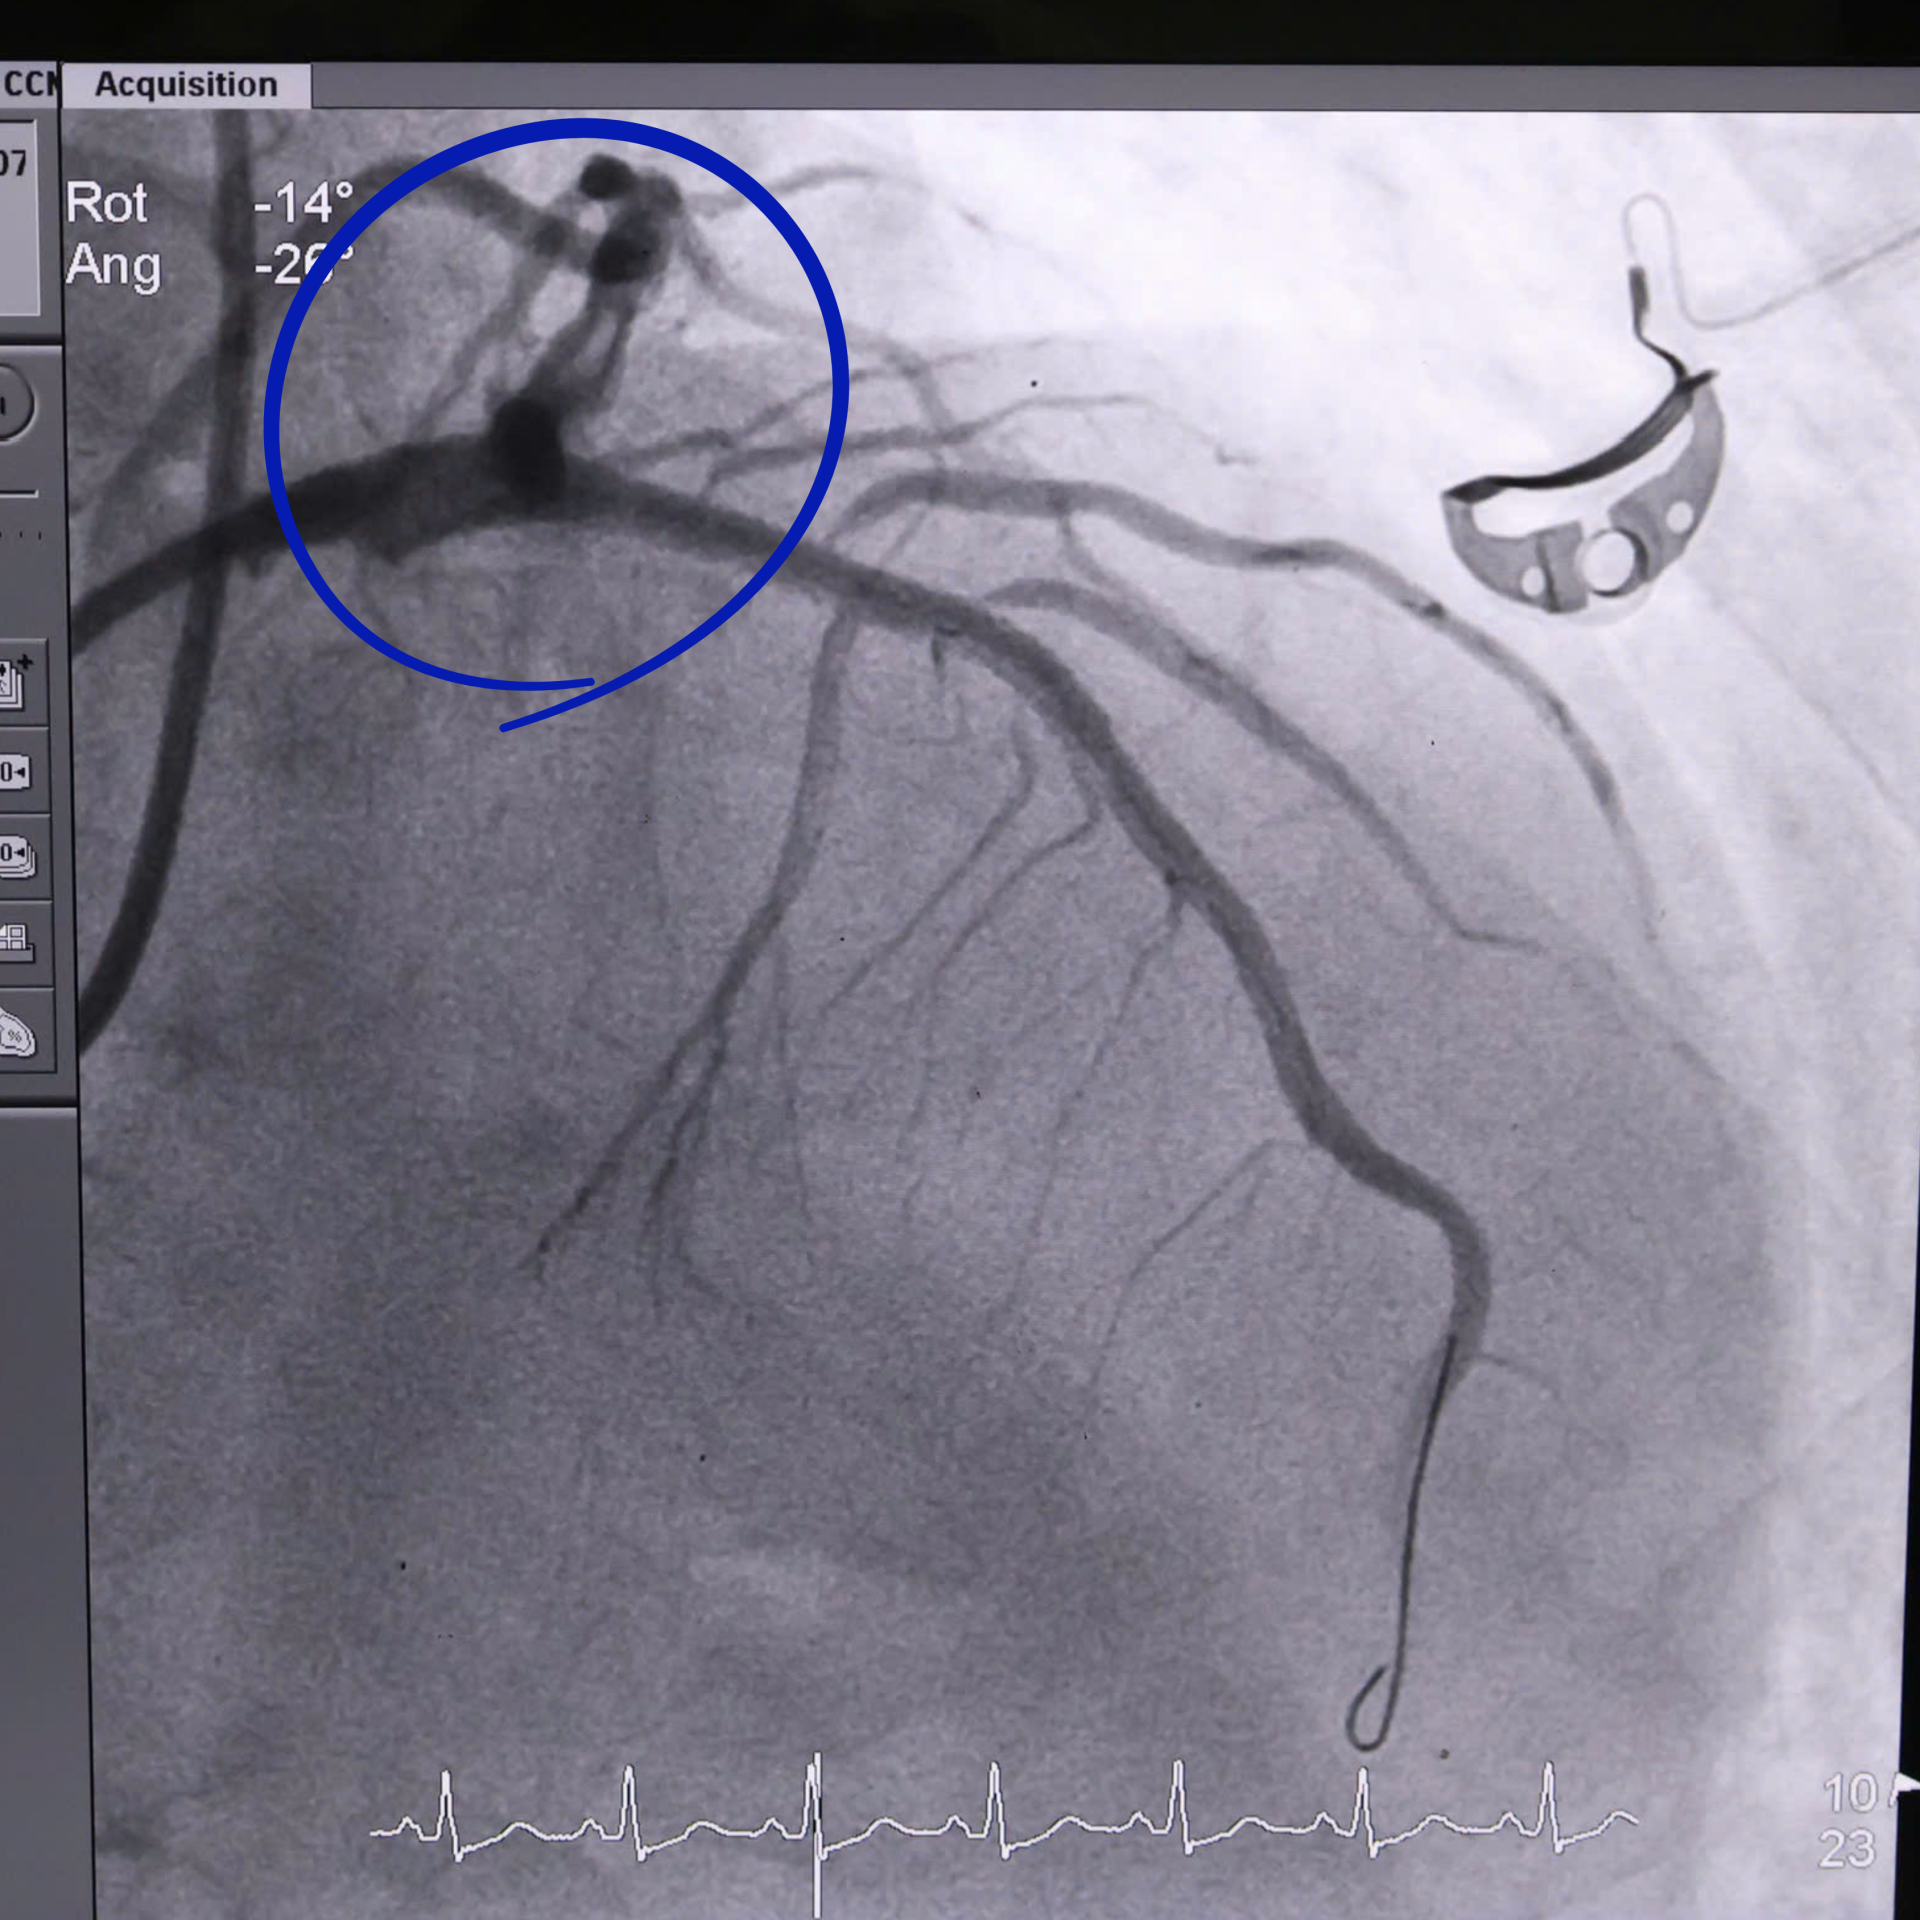

Hỉnh ảnh mạch máu được tái thông sau can thiệp.

Trước tình trạng nguy kịch của bệnh nhân, ê-kíp bác sĩ đã khẩn trương tiến hành xử lý tổn thương động mạch vành, đặt stent tái thông mạch máu nuôi. Trong quá trình can thiệp, bệnh nhân vẫn tiếp tục có những thời điểm trở nặng, ê-kíp can thiệp vừa hồi sức, vừa thực hiện kỹ thuật. Sau khi được can thiệp và điều trị tích cực, hiện nay, sức khỏe bệnh nhân đã được cải thiện, các chỉ số đều ở mức tốt.